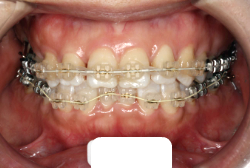

「ものがうまく噛めない」という主訴で来院したケースです。診断の結果、「骨格性反対咬合に伴う咬合不良+軽度叢生」と判明しました。原因としては特に下顎の左側が過成長したため、骨格性反対咬合になり、特に左側での噛み合わせが非常に悪くなっていると診断しました。初診時の写真を見ると、上下の正中線の大きなズレ、左側の噛み合わせの不良がはっきり分かります(黄色の矢印と緑の矢印は一致しているのが正しい状態です)。

そもそも、このような状態となっているのは骨の大きさに問題があるため生じていますので、場合によっては、「外科矯正」によって下顎の骨を外科的に縮めることで修正します。患者様が外科矯正をご希望されない場合は、従来ですと上下左右の小臼歯抜歯を行い矯正するのが普通です。

今回の患者様の場合は、「外科」も「小臼歯抜歯」も拒否されましたので、歯科矯正用アンカースクリュー(以下 アンカースクリュー)を用いて、下顎の歯列全体を後方に下げるという方法を取りました。

治療中の写真で、アンカースクリューより歯を後ろへ牽引しているのがお分かりいただけるかと思います。牽引を1年ほど続け、途中補助的に上下にゴムをかける(これを顎間ゴムと言います)手法なども追加し、全体で21ヶ月で治療を終えることが出来ました。

結局歯の本数を減らすことなく、すべてご自分の歯を残して、正しい配列と噛み合わせにすることができました。凸凹があまりひどくないため、簡単そうに見えると思いますが、このケースの初診の状態を見ると、熟練の矯正歯科医でも悩みのつきないケースです。まして、外科も出来ない、抜歯もイヤ、と言うことになると、従来の方法では治療不可能と考えられるのですが、アンカースクリューを使うことで最近は不可能が可能となってきました。